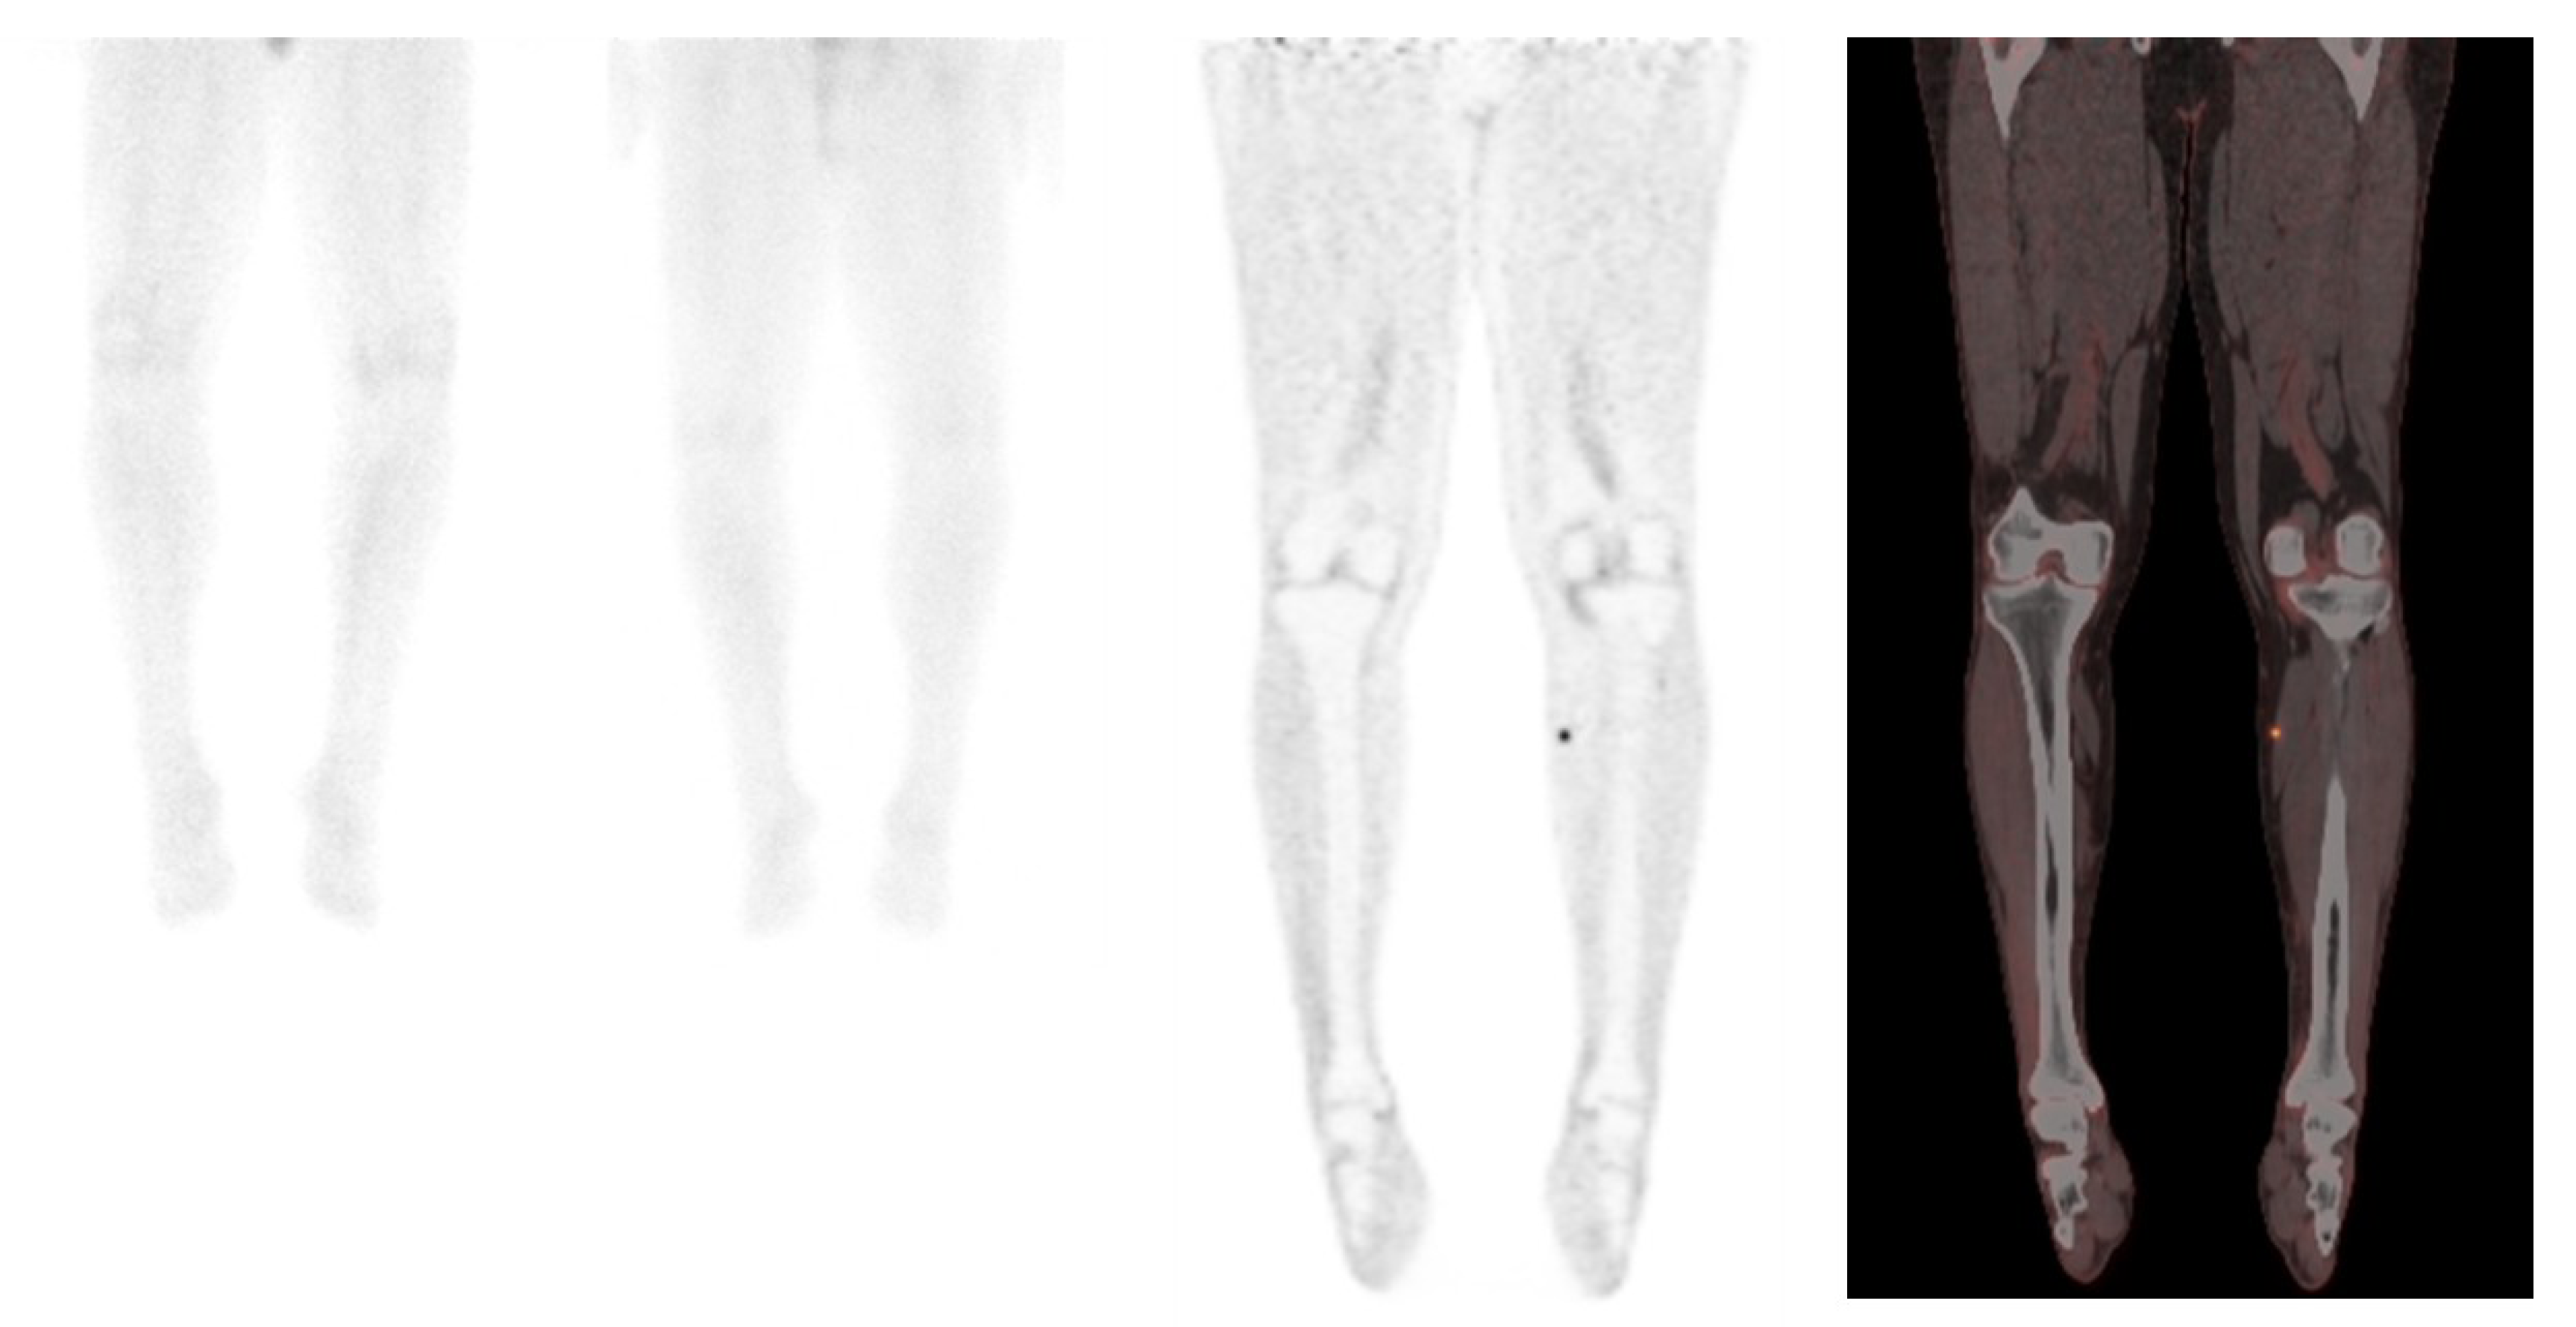

- Salavati, A.; Prasad, V.; Schneider, C.P.; Herbst, R.; Baum, R.P. Peptide receptor radionuclide therapy of Merkel cell carcinoma using (177)lutetium-labeled somatostatin analogs in combination with radiosensitizing chemotherapy: A potential novel treatment based on molecular pathology. Ann. Nucl. Med. 2012, 26, 365–369. [Google Scholar] [CrossRef]

- Schmidt, M.C.; Uhrhan, K.; Markiefka, B.; Hasselbring, L.; Schlaak, M.; Cremer, B.; Kunze, S.; Baum, R.P.; Dietlein, M. 68Ga-DOTATATE PET-CT followed by peptide receptor radiotherapy in combination with capecitabine in two patients with Merkel cell carcinoma. Int. J. Clin. Exp. Med. 2012, 5, 363–366. [Google Scholar]